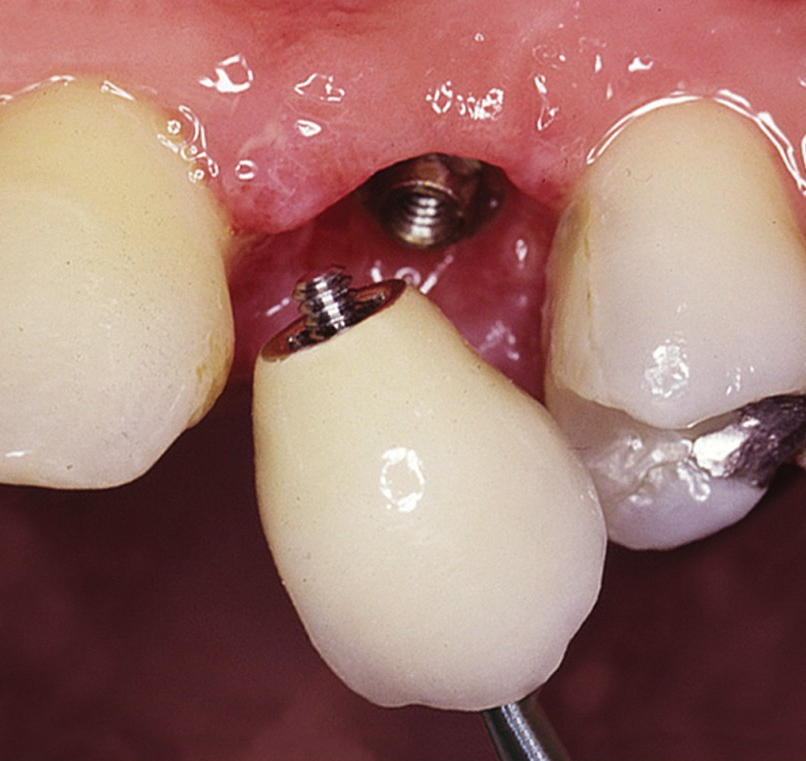

Protetické řešení může být pomocí můstku, který je kotvený na implantátech nebo pomocí jednotlivých korunek na implantátech.

V zásadě je možné do těchto můstků zařadit i přirozené zuby, zejména pokud je potřeba tyto zuby ošetřit proteticky – korunkami. Korunky nebo můstky mohou být na implantáty nacementovány nebo přišroubovány.